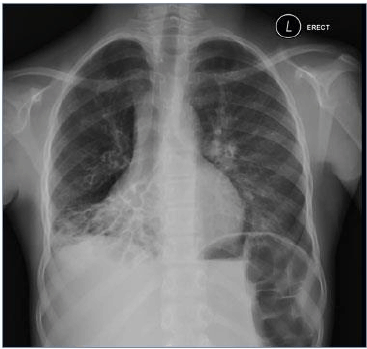

Considere a imagem radiológica abaixo:

A imagem acima, demonstra, perda de volume do lobo médio e inferior direito, com anéis de sinete típicos visíveis na região pulmonar afetada, altamente, sugestivo de: